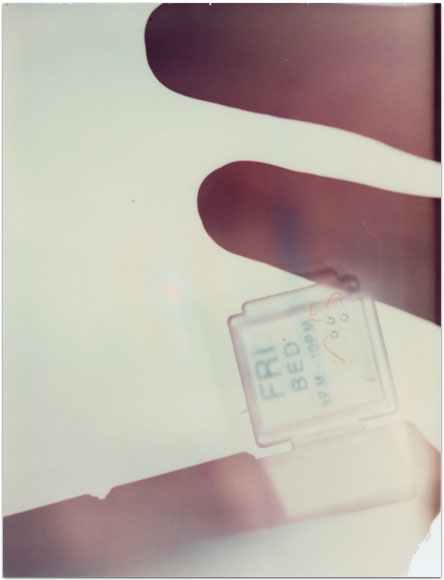

- Itis

- 2004

- 3.25″ × 4.25″

- Photographic montages of my hands & health paraphernalia on Polaroid Type 664 & 669 Film using a Daylab Printer.

- Frustrated by a lack of mobility and severe pain with my fingers, unable to accomplish any task requiring joint dexterity,

I noticed piles of health related papers strewn around. I layered these in a slide printer without removing

my hands, enlarging both onto the film.